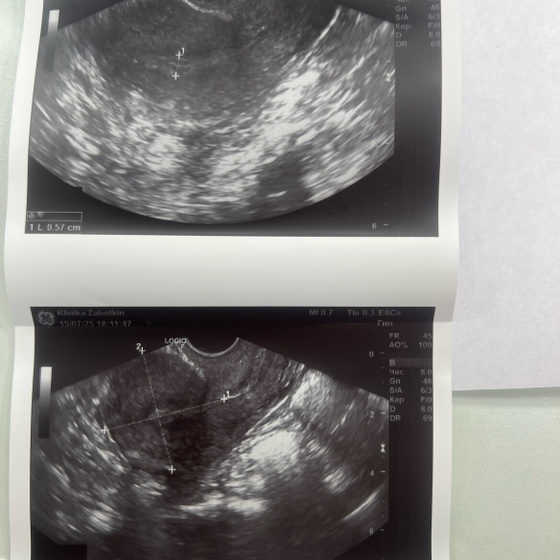

Прикреплю фото, может кто поймет, действительно ли не было овуляции? Или может еще ЖТ не успело сформироваться

Несколько циклов в год у здоровой женщины может и не быть овуляции. Это нормально. А вот эндометрий тонкий. Сейчас не стоит паниковать и заняться этим вопросом вплотную в следующем цикле. Сходите на узи до 7дня цикла, а потом в середине, что бы посмотреть эндометрий и овуляцию

У вас нет доминатного фолликула и эндометрий тонкий. Анлвуляторные циклы случаются, это не патология

К сожалению и эндометрий у вас маловат для фазы после овуляции и нет доминанта даже(